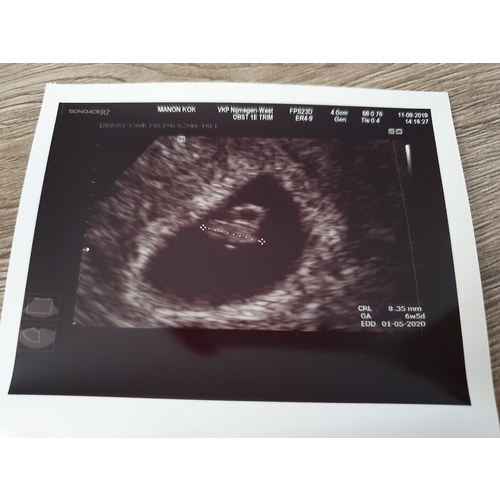

Zojuist de echo gehad: alles is goed!! Hartje klopte goed! Ik ben inderdaad gewoon wat minder ver, nu 6 weken en 5 dagen.

Ik (en mijn man uiteraard ook) ben zo blij!! Over 1,5 wk weer een echo omdat ik nu wel heel vroeg een echo heb gehad en ze rond de 8 weken wil kijken hoe het ervoor staat. Maar nu is alles perfect!